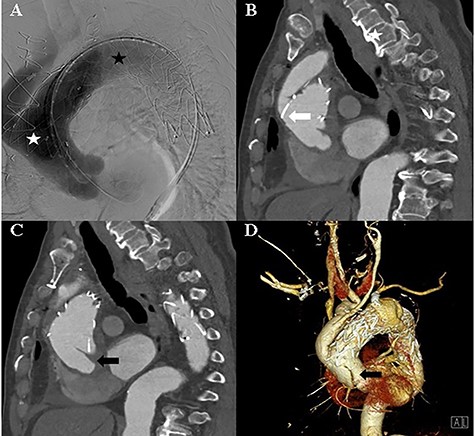

The TEVAR was performed 14 days after the debranching surgery. Under local anaesthesia, a Safari wire was placed in the left ventricle cavity. A Medtronic Valiant Thoracic Stent Graft (46 mm × 46 mm × 200 mm) was implanted in the ascending thoracic aorta and aortic arch, and a second Medtronic Valiant Thoracic Stent Graft (42 mm × 42 mm × 200 mm) was implanted in the aortic arch and descending thoracic aorta. The left subclavian artery was plugged with an Amplatzer Vascular Plug (16 mm) (Fig. 2).

A: Aortic angiography during TEVAR shows the thoracic graft implanted in the ascending thoracic aorta and aortic arch (white asterisk) and the thoracic graft implanted in the aortic arch and descending thoracic aorta (black asterisk). B: Computed tomography of the post-TEVAR shows the placed thoracic graft (white arrow). C and D: Computed tomography of the post-TEVAR shows the intimal dissecting flap at the proximal ascending aorta.